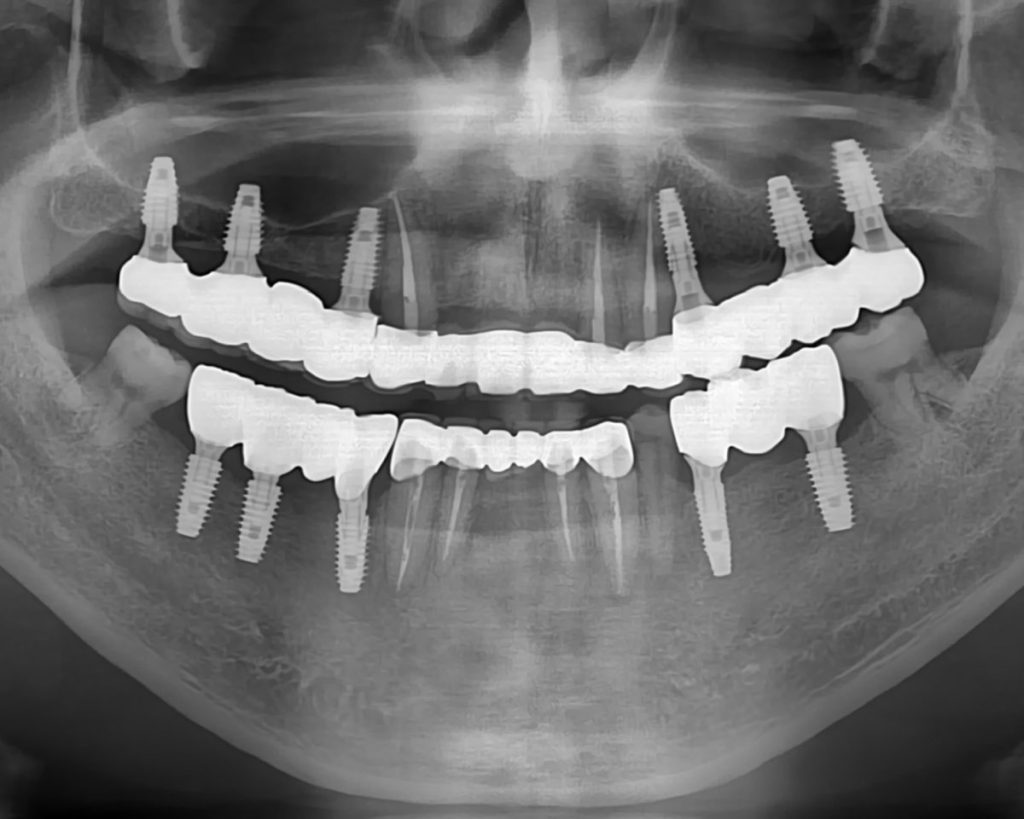

정확성과 예후까지 고려한 ‘디지털 임플란트’

어디에 어떻게 심느냐가 수명을 결정합니다.

0.01mm 단위로 위치·각도·깊이까지 정밀 설계합니다.